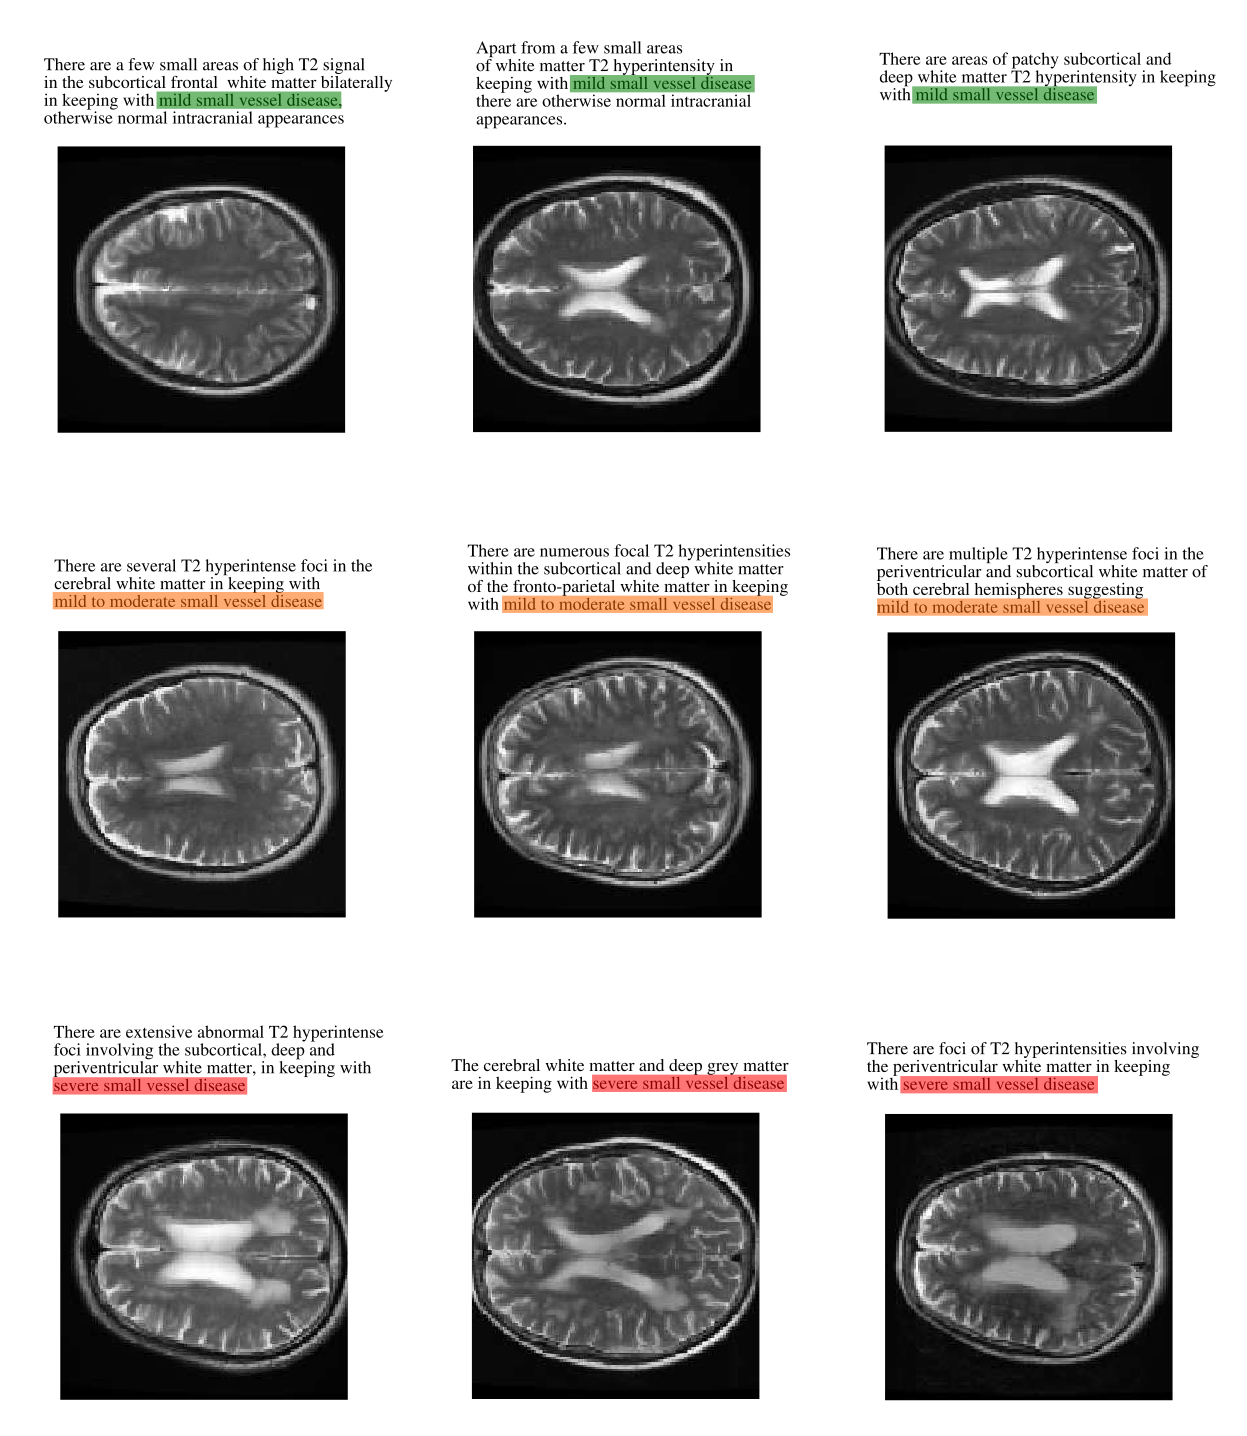

Refer to caption

Figure S3: Comparison between ‘mild’, ‘mild to moderate’, and ‘severe’ small vessel disease (SVD). In most cases, our model was able to correctly classify SVD; however, equivocal cases (e.g., ‘mild-to-moderate’, which had been labelled by our team of neuroradiologists as ‘abnormal’ to encourage model sensitivity) were sometimes misclassified. Similarly, equivocal cases involving atrophy and enlarged perivascular spaces were sometimes misclassified. Given the degree of subjectivity involved, however, these errors are highly unlikely to have a significant clinical impact.